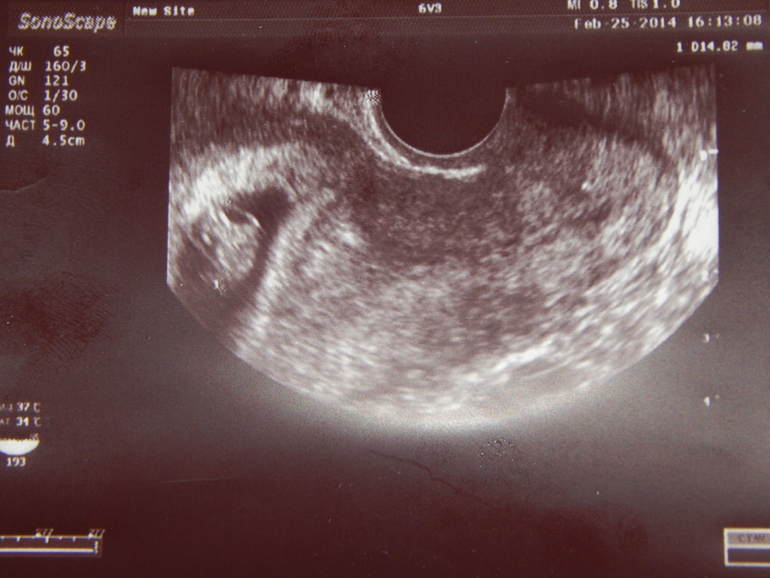

Вопросы про УЗИ, обследования и анализы: что, где, как, когда?Не выдержала до 12 недели. Вчера потопала на узи. Теперь я сама уже верю, что беременна )) Так клево было смотреть на то как бьется сердечко - туктуктук. Быстро быстро. Расстроили что в яичнике обнаружили кисту. Двухкамерное анэхогенное образование 39*28.

Итак, вот мой хвостатый червячок.

НА человечка не похож пока )